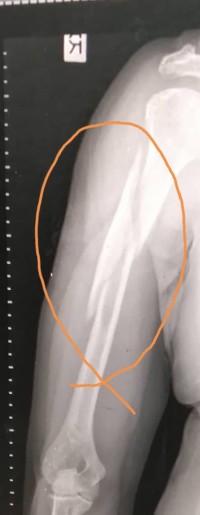

骨折 成功案例-骨折摔倒受伤而导致骨折 By 金山豪猪枣January 11, 2025Less 1 min read234 Views 今年74岁的钟女士,数月前走下石级时摔倒受伤而导致【骨折】,如上图之x光图片!后经医院治疗,服用金山豪猪枣而无需再服食西药(消炎止痛药、抗生素),《骨折伤口处》无发炎及疼痛感,骨折愈合快速,医院之骨科专家医生均深感惊奇无比!👌💯👍 ShareTweetShareShare Previous Post成功案例-新冠疫情 Next Post成功案例-中风 你可能会喜欢的阅读 Nothing Found! Ready to publish your first post? Get started here.